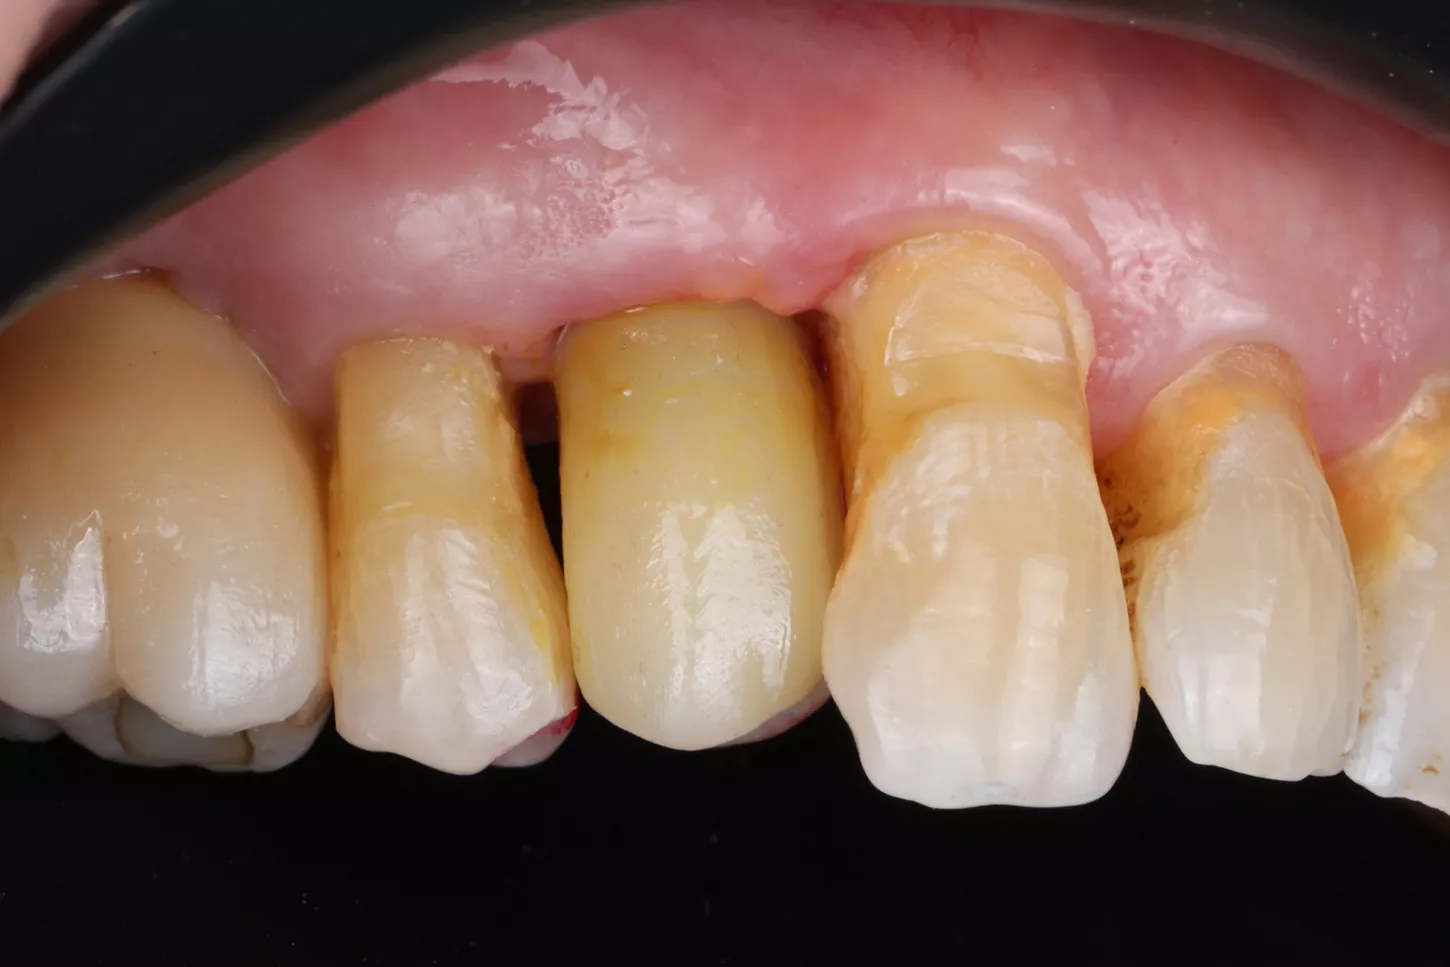

A 78-year-old male in good general health, with no medication and a negative smoking history, presented with mobility of the maxillary right second premolar (tooth 15) (Fig 1a. 1b). Clinical examination revealed severe occlusal wear, plaque accumulation, subgingival calculus, bleeding on probing, and multiple carious lesions. Periodontal assessment showed probing depths >10 mm and grade III mobility. CBCT confirmed circumferential vertical bone loss around tooth 15 and generalized periodontal involvement, indicating a hopeless prognosis and the need for extraction (Fig 1c).

1a. 1b. 1c. CBCT and panoramic views showing severe bone loss around tooth 15, confirming hopeless prognosis.